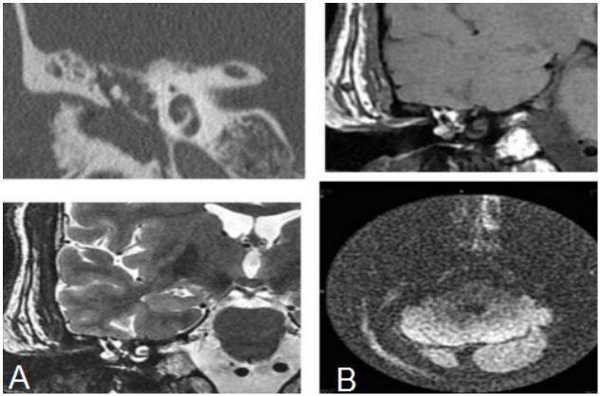

КТ (А) и МРТ(В) - картина холестериновой гранулемы

Эта дилемма волнует многих пациентов, но вид исследования выбирает лечащий врач, опираясь на результаты предыдущей диагностики и на конкретные жалобы. Отказываться от КТ уха из-за ложных соображений о вреде процедуры не стоит, современные мультидетекторные томографы позволяют минимизировать влияние лучевой нагрузки для большей категории лиц (исключение - беременные и дети, не достигшие 14 лет). В ряде наблюдений, особенно, если визуализируется опухолевый процесс, может понадобиться и МРТ, и КТ уха - эти способы взаимодополняют друг друга. Выполнение магнитно-резонансного сканирования обосновано, если после проведенной КТ остались сомнения в диагнозе. МРТ лучше демонстрирует менингоцеле, холестеатому, неврит лицевого нерва, внутричерепную патологию, вызванную процессами в среднем ухе, что не всегда показывает компьютерная томография высокого разрешения. КТ среднего уха часто не способна визуализировать степень возможной облитерации улитки после перенесенного воспаления или отдаленные последствия перелома височной кости. Точная оценка состояния имеет решающее значение для планирования кохлеарной имплантации.

Опухоль яремного гломуса на КТ височных костей

Кости содержат мало воды, поэтому под действием магнитного поля не преобразуют радиочастотный сигнал. Особенности оборудования не позволяют использовать его для обследования черепа при подозрении на переломы. МРТ предпочтительней для изучения церебральной паренхимы, мозговых оболочек, нервных волокон, сосудов.